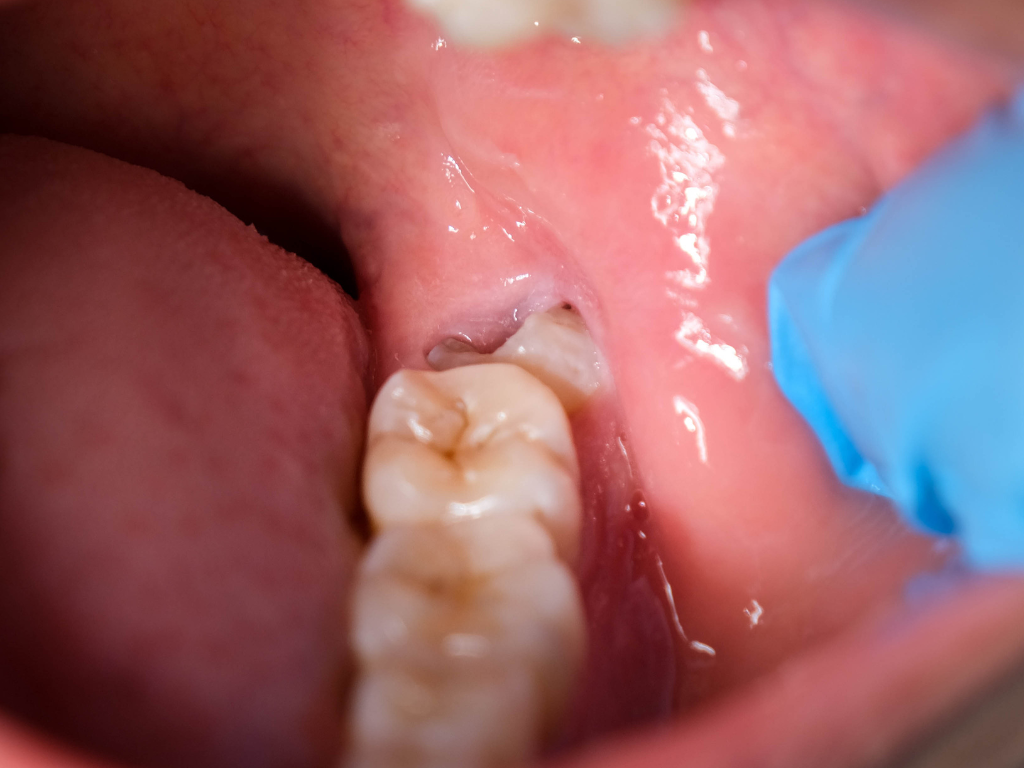

✔ 横向きに埋まっている

✔ 半分だけ出ている

横向きや半埋伏(半分だけでている)の親知らずは、

・歯ぐきの炎症(智歯周囲炎)

・強い腫れや痛み

・口が開きづらくなる

・隣の歯の虫歯・歯周病になる

などの原因になることがあります。